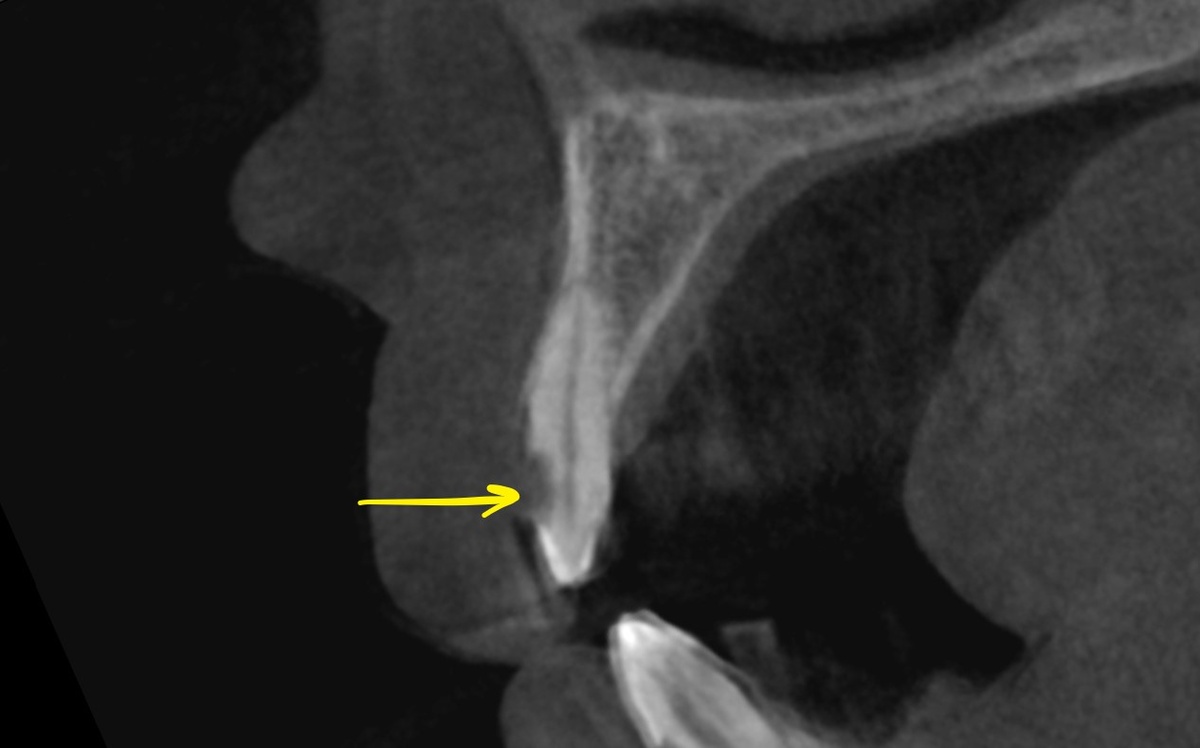

На сежих срезах КТ прекрасно видно:

• пломбы находятся вплотную к пульпарной камере;

• плотное краевое прилегание;

• отсутствие вторичного кариеса.

Всё это при далеко не идеальных условиях - прикус требует коррекции, нагрузка избыточная. Но правильный протокол лечения позволил сохранить витальность.